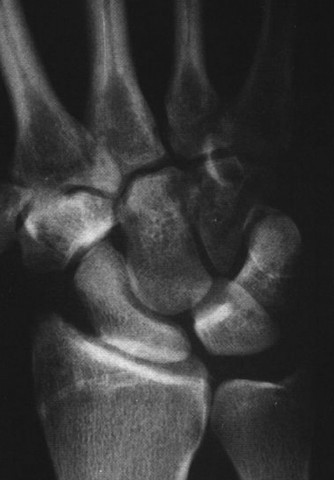

CASE 11 ### A patient presents to your clinic with ulnar-sided wrist pain. X-ray is as shown in Figure 3–10. What is your diagnosis?

Figure 3–10(©) Sunil Thirkannad and Christine M. Kleinert.

The correct answer is (D). The findings in the radiographs are consistent with pisotriquetral arthritis.